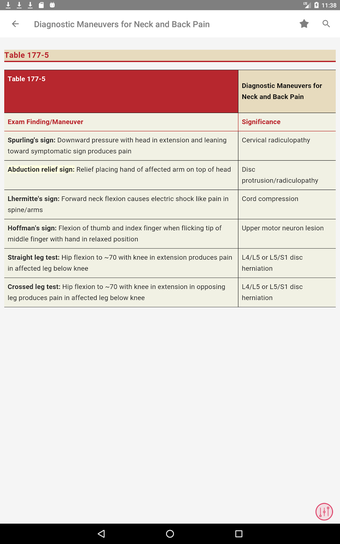

最初に知っておくべきことは、ティンティナリの緊急医療マニュアルが緊急医療の最も重要なトピックについてすべてを提供する包括的なガイドであることです。これは、医師、看護師、および救急医療技師にとって理想的なアプリです。

この無料アプリには、日常の実践に役立つ多くの情報が含まれています。このアプリでカバーされるトピックは、疾患から薬剤、さまざまなタイプの傷害まで幅広く、患者ケアを担当する人々にとって素晴らしいリソースです。